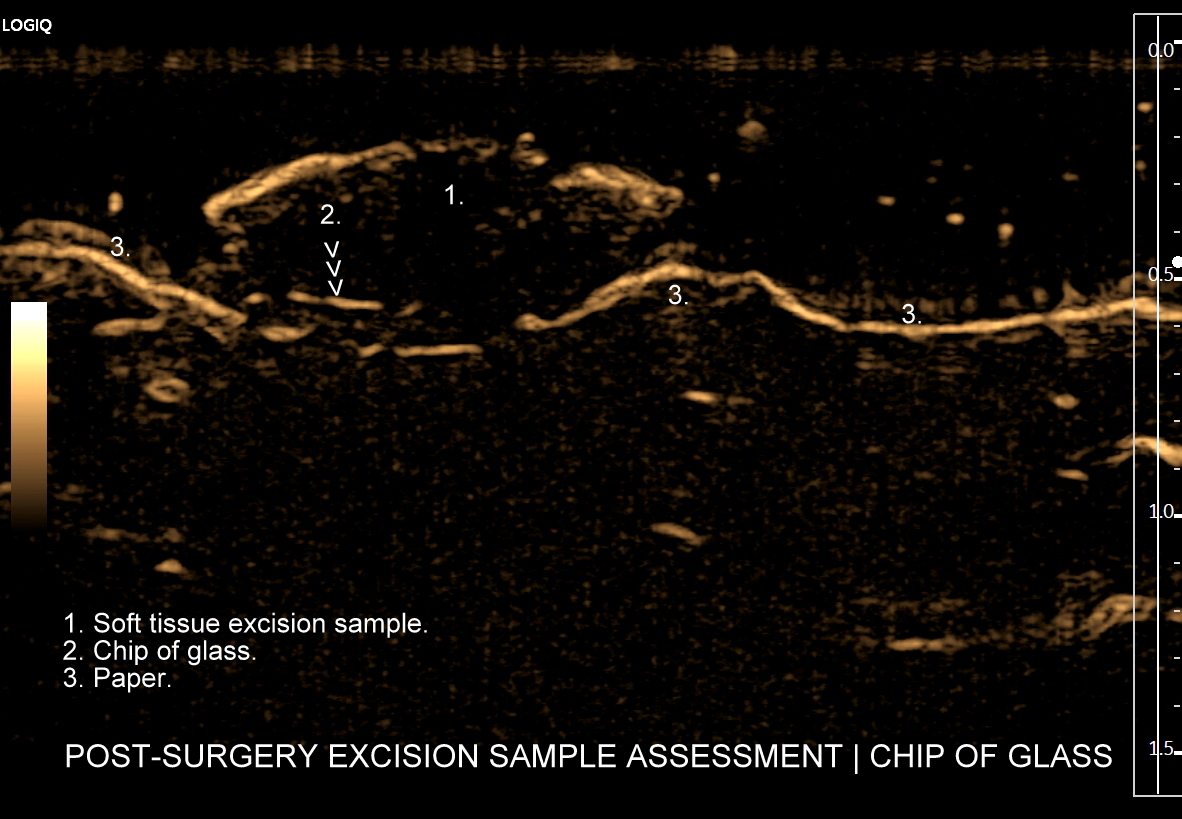

Tryb B-flow to modalność obrazowania w ultrasonografii, która dostępna jest w aparatach firmy GE. Oparta jest o technologię polegającą na selektywnym wzmacnianiu sygnału poruszającego się obiektu i jednoczesnej supresji sygnału z obiektów stacjonarnych. W związku z powyższym metoda może być wykorzystywana do obrazowania płynącej krwi, zarówno w naczyniach dużych, jak i w naczyniach mikrokrążenia, a także poruszających się tkanek i materiałów litych.

Tryb B-flow wyjątkowo korzystnie sprawdza się także przy badaniu wnętrza dużych i średnich naczyń. Otóż umożliwia on pewne zobrazowanie drożności naczynia, umożliwia wykazanie obecności / lokalizacji naczynia przy niesprzyjających warunkach obrazowania w trybie B, a poza tym uzyskiwane w omawianym trybie obrazy zarysów błony wewnętrznej naczyń (np. tętniczych blaszek miażdżycowych, skrzeplin przyściennych, zmian w przebiegu dysplazji włóknisto-mięśniowej, czy zapaleń tętnic) charakteryzują się wysoką rozdzielczością i kontrastowością. Skany dużych naczyń w trybie B-flow przypominają wręcz te uzyskiwane w klasycznej angiografii opartej o promieniowanie rentgenowskie. B-flow wykorzystywany może być praktycznie i rutynowo do obrazowania naczyń szyi i kończyn, naczyń wątroby, naczyń trzewnych, nerkowych oraz dużych naczyń brzusznych.

Oprócz zastosowań stricte naczyniowych tryb B-flow znajduje zastosowanie przy poprawie obrazowania struktury narządów wewnętrznych i ich zarysów. Otóż wykorzystując zasady powstawania obrazu w tym trybie, tj. generowanie silnego sygnału, który odpowiada poruszającemu się elementowi, przy implementacji delikatnych acz zdecydowanych ruchów głowicą USG, w ruch można wprawić cały narząd lub grupę sąsiadujących struktur, przez co możliwe staje się stworzenie obrazów struktur miąższowych oraz całych narządów. Jednocześnie stosując odpowiednio intensywny ruch litych struktur tkankowych można niejako oszukać software, tj. oprogramowanie aparatu dokonuje supresji sygnału poruszającej się krwi, przez co uzyskuje się obraz danego narządu o znacznie większej kontrastowości i szczegółowości aniżeli w podstawowym obrazowaniu w skali szarości (w trybie B).